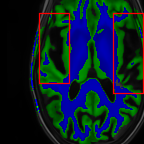

Sparsity LI 2D CNN 3D CNN Ours GT

4 Refer to caption (a) 0.6787/0.7972 Refer to caption (b) 0.8143/0.8776 Refer to caption (c) 0.8190/0.8714 Refer to caption (d) 0.8664/0.9085 Refer to caption (e) GM/WM

Refer to caption (f) 0.6808/0.7161 Refer to caption (g) 0.8103/0.8631 Refer to caption (h) 0.7950/0.8606 Refer to caption (i) 0.8598/0.9115 Refer to caption (j) GM/WM

Figure 6: Visual comparison of gray matter (Green)/white matter (Blue) segmentation over different methods, with respective DICE scores listed under the images.

In Fig. 6, we demonstrate the advantage of the proposed method in brain matter segmentation. It is clear that although 2D and 3D CNN generates visually plausible interpolation as presented in Fig. 5, the brain matters are easily misclassified due to incorrect anatomical structures and blurred details.